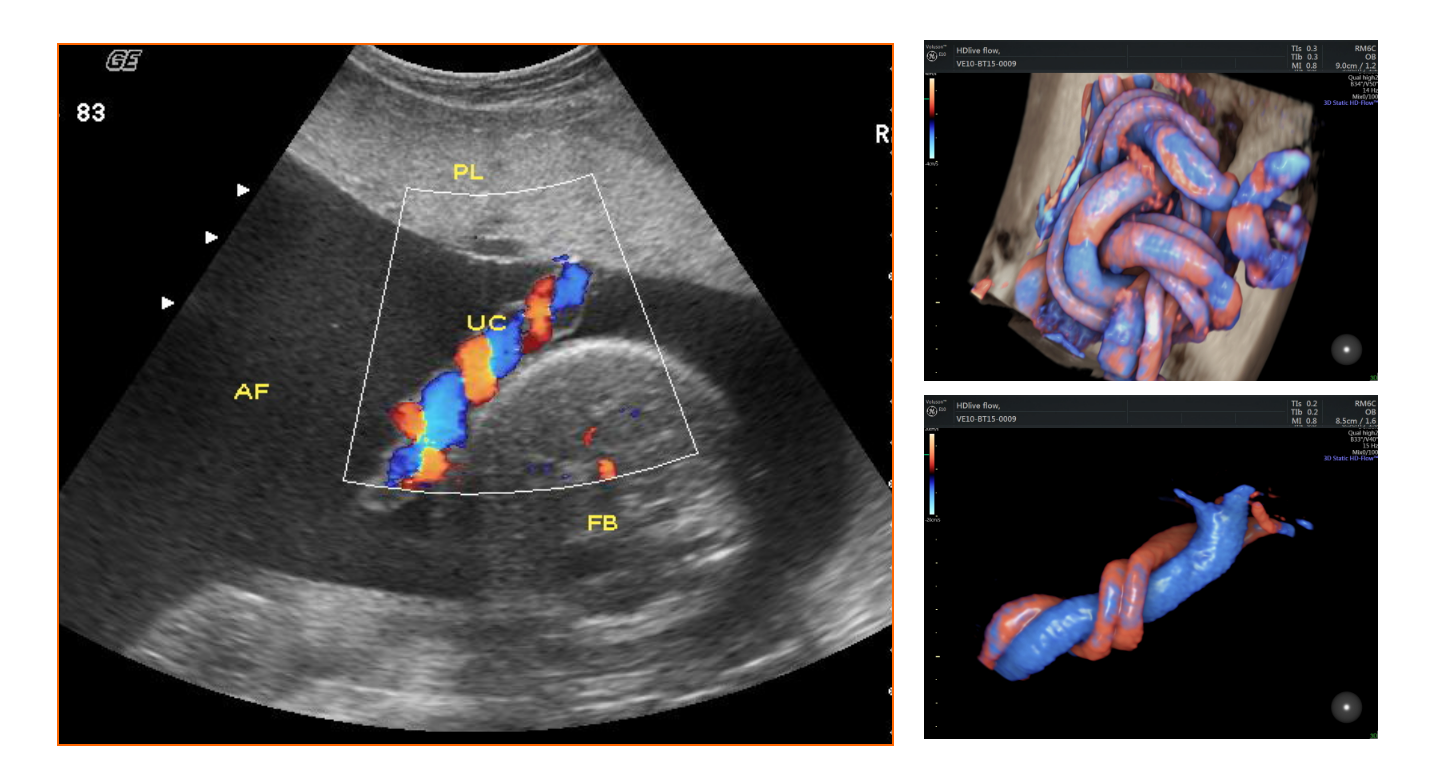

正常中晚期妊娠声像图

• 4.4 异常妊娠声像图